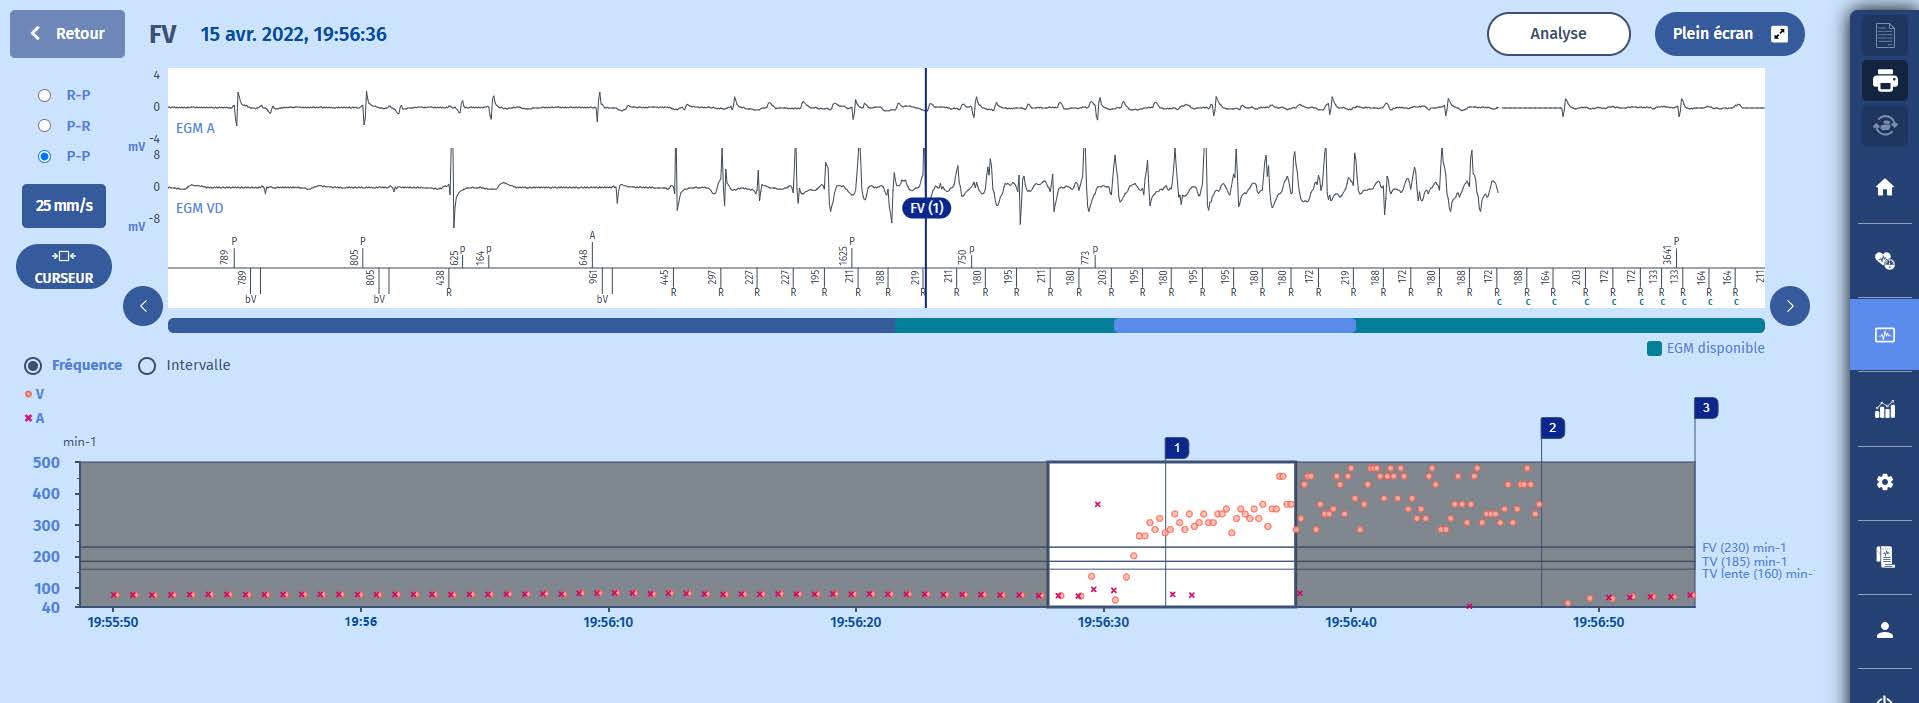

Electrogramme

1 Le tracé confirme l'apparition d'une fibrillation ventriculaire très rapide (FV (1)) détectée au-dessus de 255/min (300/min), et déclenchant une charge des condensateurs (marqueurs C) après une persistance de 20 cycles. L'épisode de FV est parfaitement

détecté.

2 Tout au long de la charge, la majorité de la FV est analysée cycle par cycle et la charge se poursuit tant que la majorité de la FV ne passe pas à la TSV/ST ou à la RS (rythme lent).

3 Une fois la charge des condensateurs terminée (42 J), le choc (37,7 J) est délivré après un cycle de confirmation qui se déroule également dans la zone de FV. Le rythme lent est rétabli avec la détection auriculaire et la stimulation biventriculaire.

4 Le fonctionnement ici est un cas d'école : détection parfaite de tous les signaux, diagnostic correct, initiation rapide de la thérapie, choc efficace, mémorisation de l'épisode.